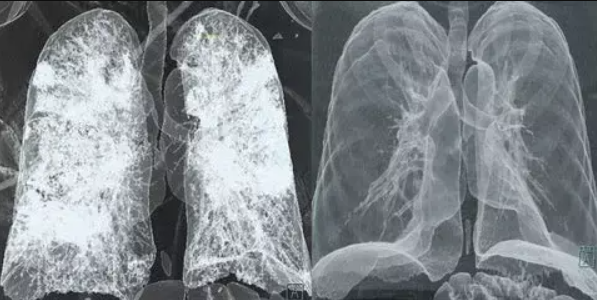

If left unchecked, this toxic mucus can:

❌ Harden and block your airways, causing terrifying breathlessness

❌ Trap harmful bacteria and fuel infections

❌ Trigger relentless inflammation, worsening COPD, asthma, or bronchitis

❌ Shrink your lung capacity, turning daily life into a constant struggle

Stage 1: The Mucus Trap

Everyday exposure to harmful airborne toxins triggers your lungs to overproduce sticky mucus as a defense mechanism.

But instead of protecting you, the mucus traps more toxins—blocking your airways and triggering endless coughing.

Stage 2: The Airway Squeeze

Over time, this mucus hardens into thick, sticky layers that narrow your airways.

Result? Oxygen deprivation that leaves you breathless, fatigued, and weak—turning simple activities into exhausting struggles.

Stage 3: The Dangerous Spiral

Trapped mucus becomes a breeding ground for bacteria and viruses, leading to chronic infections, inflammation, and permanent lung damage.